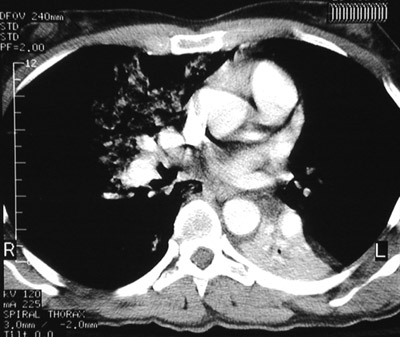

| These views above amd below from a chest CT scan reveal an aspiration pneumonia involving the right middle lobe. Note the ground glass opacifications and the bronchial hypodense material. In the view below is an area of left lower lobe consolidation from a prior aspiration followed by pneumonia. |